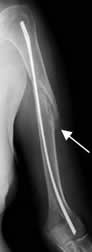

Fig 85. Cicatrización por primera intención.

Rx AP. Fractura espiroidea en la diáfisis humeral, estabilizada con clavo de enders. Hay incipiente formación de callo óseo, secundario a la cicatrización por primera intención.